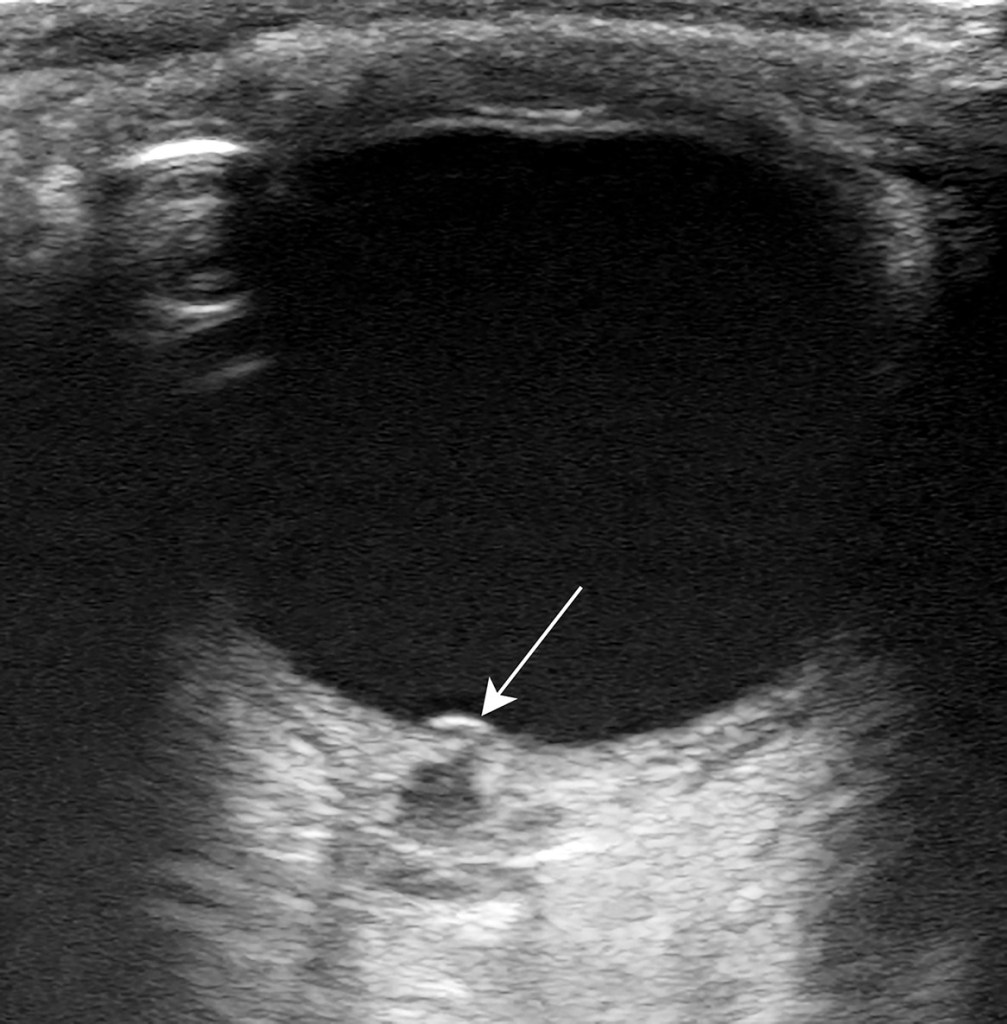

Pigtail Catheter vs Large Bore Chest Tube for Pneumothorax

- We agree with the author’s conclusion. PC performed as well as LBCT in terms of successful drainage and was associated with fewer complications, decreased drainage duration, and decreased length of hospital stay, driven by data on spontaneous pneumothorax.